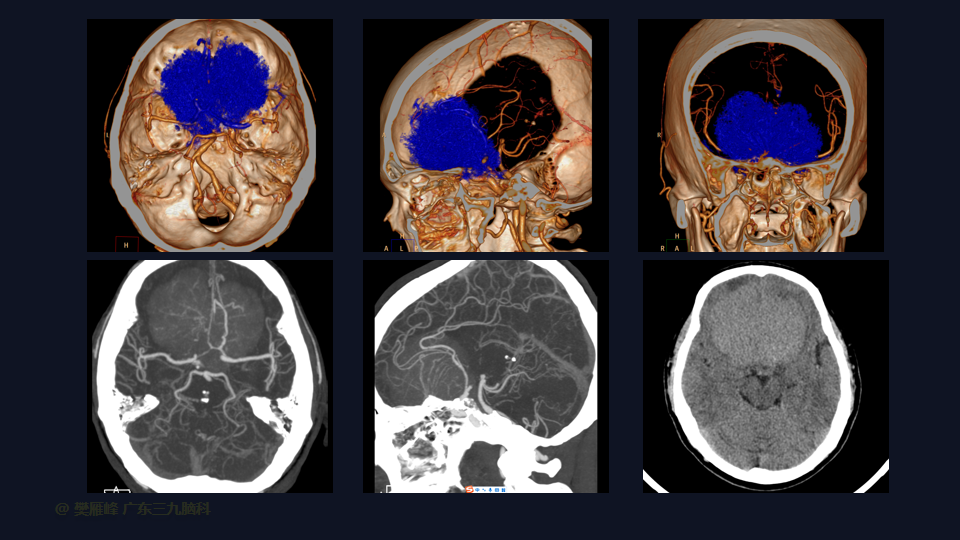

嗅沟和蝶骨平台脑膜瘤的血供来源于硬脑膜、骨和软脑膜。主要来源于脑膜中动脉前支供血,也可以通过筛前和筛后动脉(通常起源于眼动脉)的颈内动脉(ICA)分支供血。

在这个二维手术视频中,展示了一种经前纵裂额底入路切除巨大嗅沟脑膜瘤的方法。患者是一名52岁的男性,有双眼视物模糊3月、无步态不平衡病史,神经影像学显示前颅窝、双侧鞍旁、桥前池示一巨大团块状等T1长T2,FLAIR序列高信号,明显强化,其内示多发流空信号影,邻近双侧颈内动脉及双侧大脑前动脉被包绕,大小约77×62×51mm的嗅沟脑膜瘤。术中实现肿瘤全切除。术后3月双侧嗅觉基本同术前,双侧视力较术前好转,神经影像学显示肿瘤全切。我们展示了安全的颅神经和肿瘤切除术的细微差别和技术要点,包括:采用降低硬膜开口的颅底法,保留额叶静脉,防止静脉损伤。诊断时,尽管患者嗅觉常常缺失,但仍有至少保留一根嗅觉通路。通过精准的解剖重视A2段的保护。最后,需要多层重建颅底。